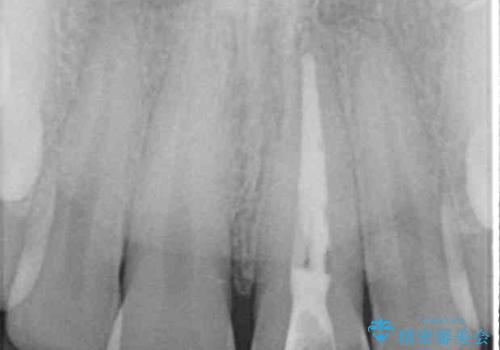

- 神経を取り除いたことで変色した前歯を気にして来院された患者様です。

根管治療はやり直さずに、ファイバーポストを使用した土台を植立してオールセラミッククラウンにて補綴することとしました。